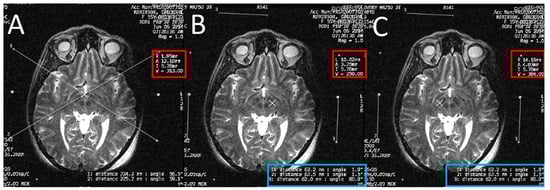

A high-resolution MRI of the patient’s brain with 3-tesla scanner (Signa 3T94 VHi; General Electric Medical Systems, Milwaukee, WI, USA) was done. Two main sequences were obtained. The first is a 3D T1-weighted, spoiled gradient echo imaging of the entire head (section thickness: 2 mm; field of view: 26 × 26 cm; TR: 7.0–8.0 ms; TE: ~400 ms; flip angle: 12; band width: 31.25 KHz; acquisition time: <7 min). The second sequence is high-resolution, contiguous, T2-weighted, fast spin-echo imaging through the region of the midbrain and basal ganglia (section thickness: 1.5 mm; slice interval: 0 mm; matrix size: 512 × 512; field of view: 26 × 26 cm; TR: 4600–6200 ms; TE: 95–108 ms; acquisition time: <5 min) (Figure 2).

Figure 2. An axial T2 weighted magnetic resonance imaging (MRI) image at the level of the subthalamic nuclei (STN).

Figure 5. Calculating the subthalamic nucleus (STN) coordinates from the magnetic resonance imaging (MRI) console. (A) Two diagonal lines intersecting at the center of the frame at the STN level with MRI coordinates of the center of the frame shown inside the red square; (B) a crosshair at the center of the left STN, with its MRI coordinates shown inside the red square; two lines are drawn between the middle and lower fiducials on both sides of the frame and their lengths (in the blue rectangle) are used to calculate the Z coordinate; (C) a crosshair at the center of the right STN, with its MRI coordinates shown inside the red square; two line are drawn between the middle and lower fiducials on both sides of the frame and their lengths (in the blue rectangle) are used to calculate the Z coordinate.